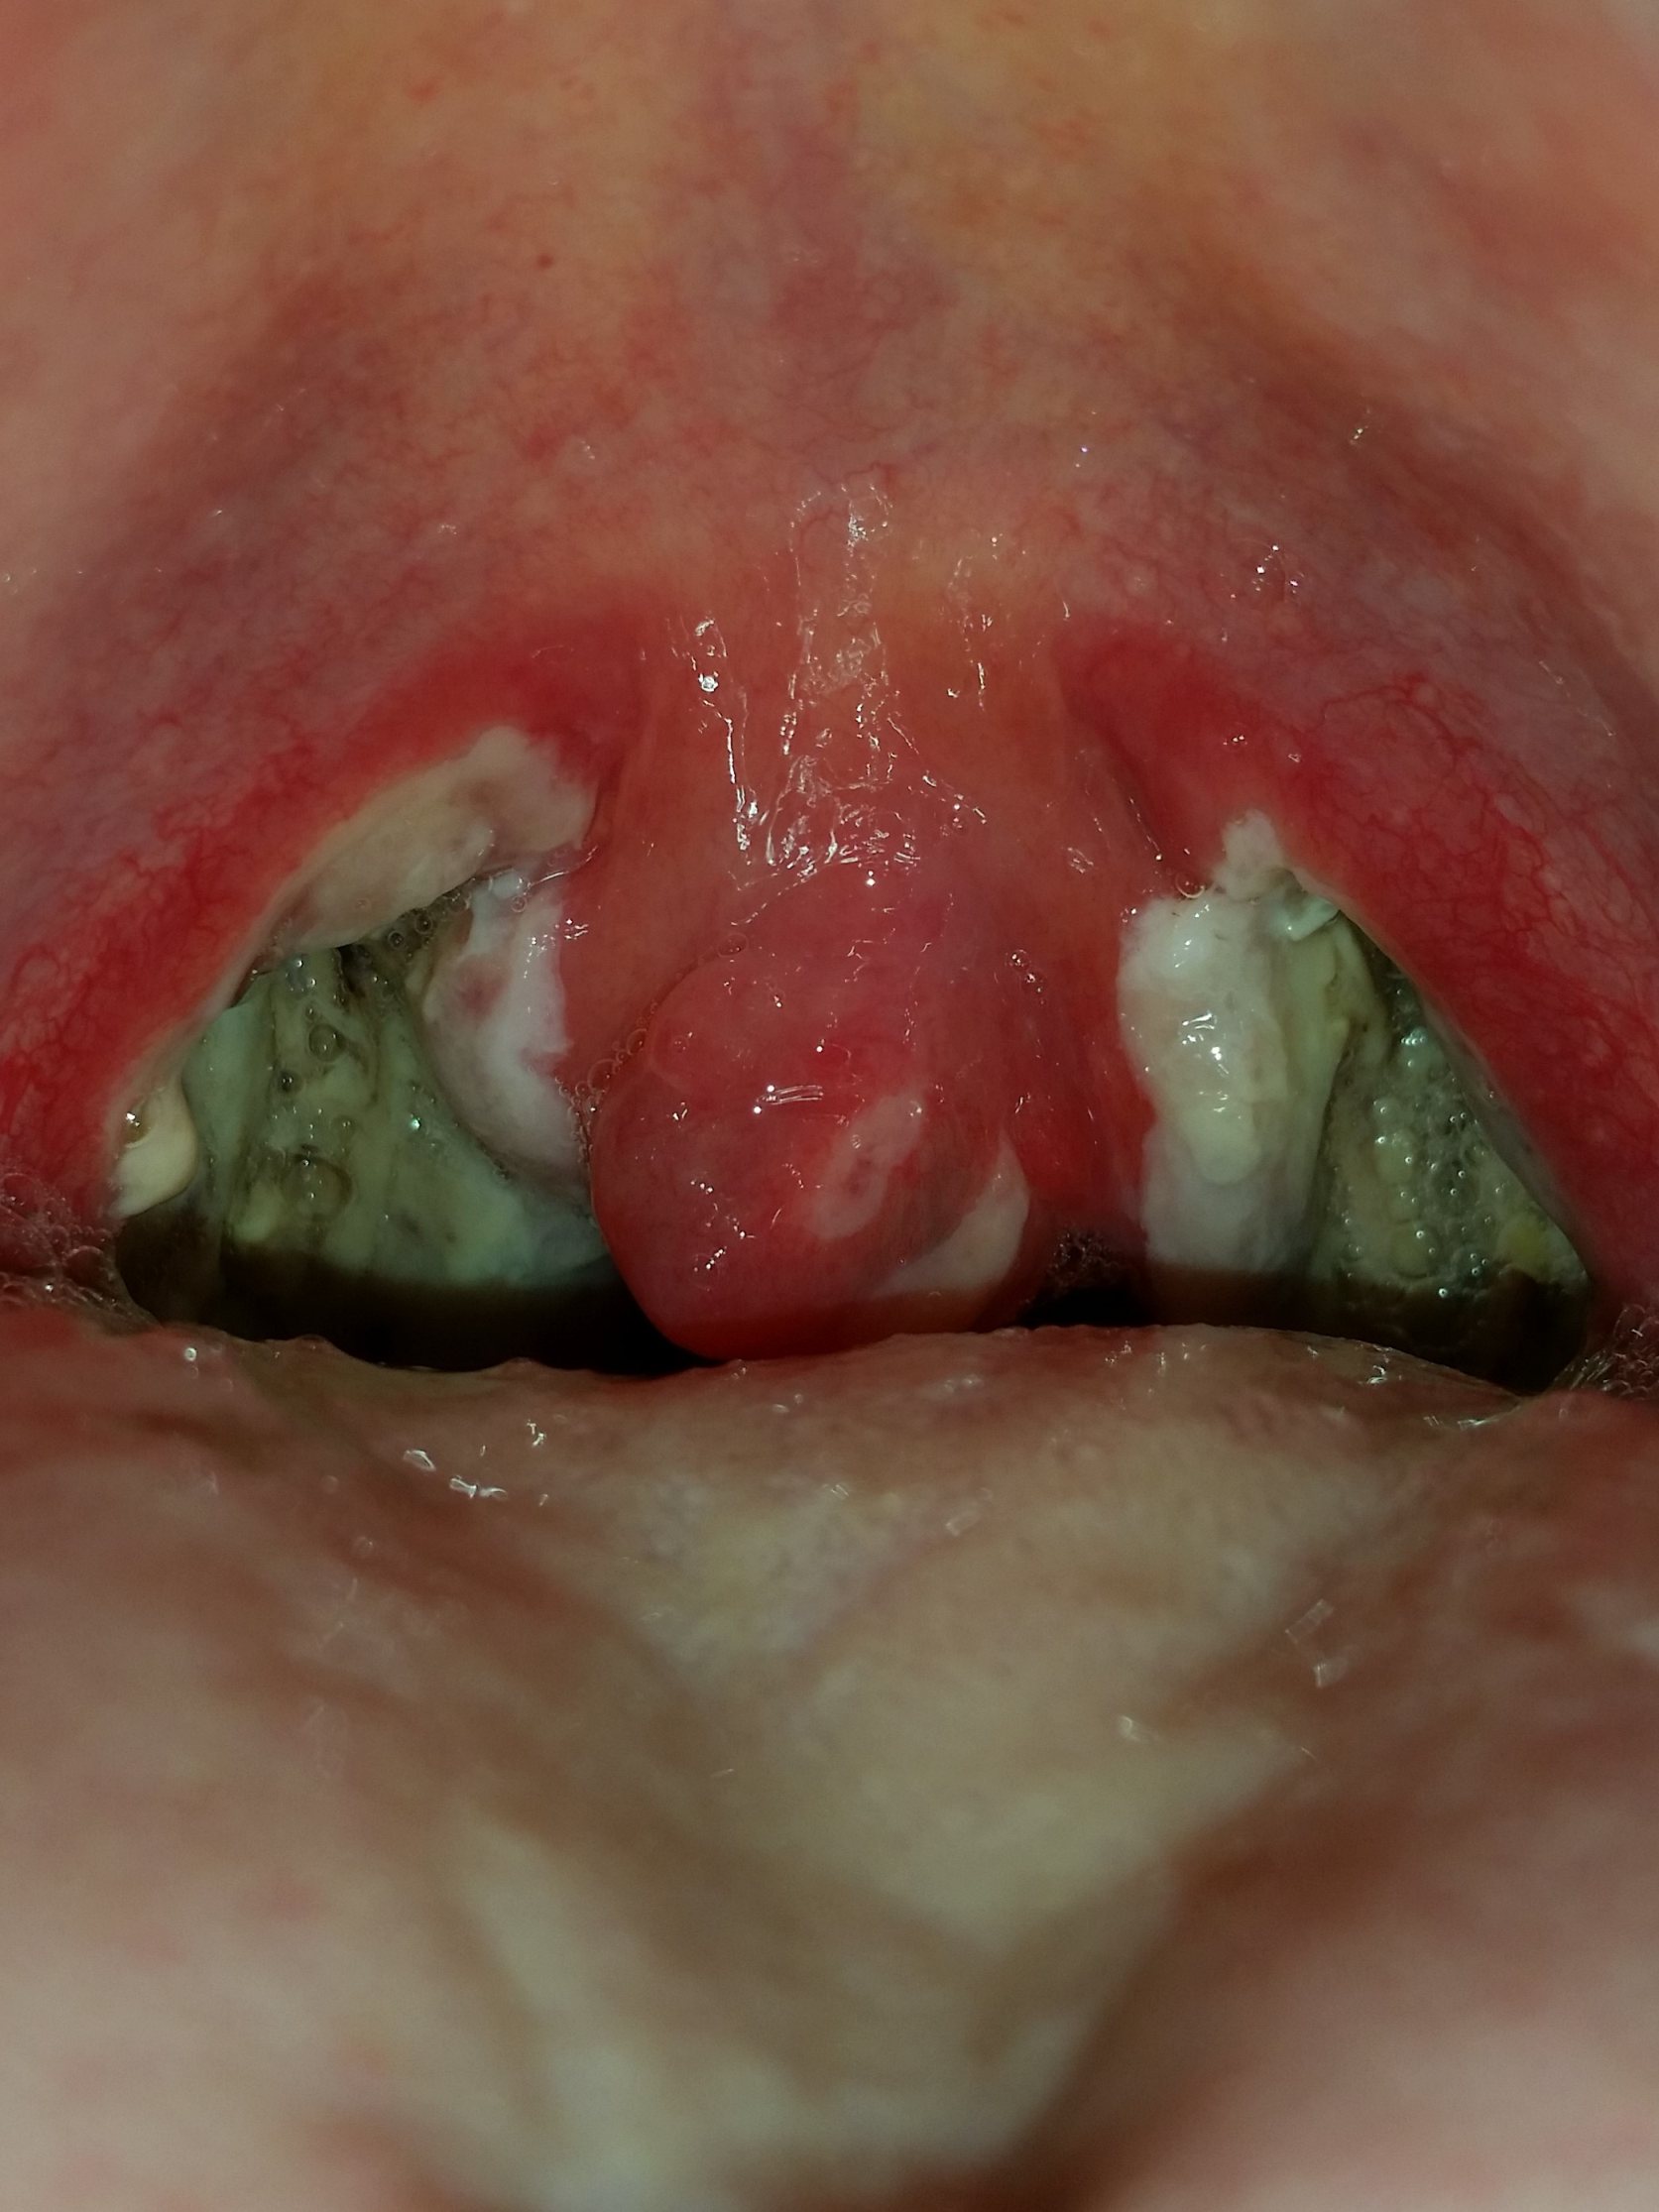

Mandel OP – Bilder Dokumentation Heilungsprozess

- Mandeloperation Tag 3

Nach der Operation bildeten sich direkt die weiß, grünlichen Beläge (Fibrinbeläge).

Ab dem Tag 9 lösten sich langsam die Beläge. (Ein ziemlich brennendes Gefühl)

Ab dem Tag 14 hatten die Schmerzen nachgelassen, sodass ich die Schmerzmittel Dosierung senken konnte.